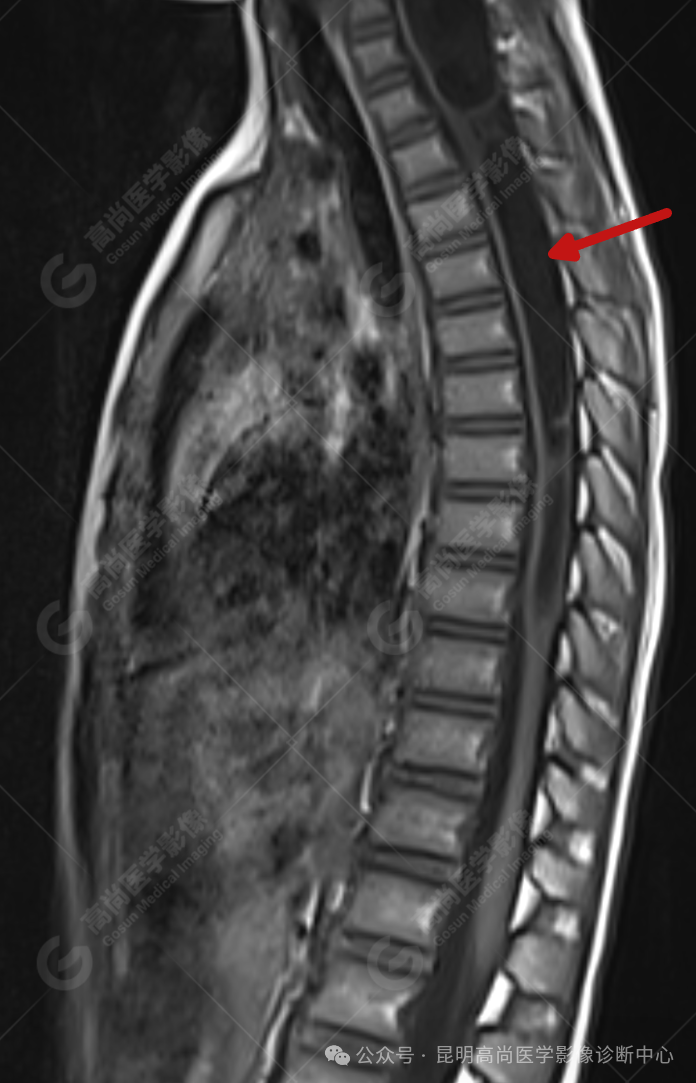

患者女,5 岁,出生时发现颈部包块,大小 3 cm×3 cm,5 年来无变化,拟行手术治疗,要求增强核磁协诊,否认体内金属物,无过敏史。

影像表现

颈 3-5 层面颈后部软组织不规则片状异常信号影,脊膜膨出可能;颈 3、4 棘突局部显示不清;颈胸髓内(约颈 3-胸 9 椎体水平)异常信号影,考虑囊肿并局部颈髓空洞可能,肿瘤或其他待排;请结合临床及相关检查。